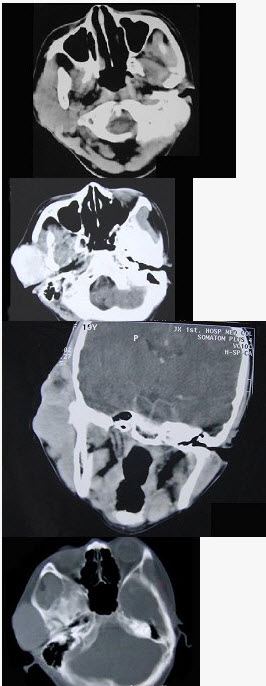

- 单项选择题19岁,女性患者,右侧面颊部肿胀一年,CT检查如图所示,请选择最佳答案()。

A、右颊部神经纤维瘤

B、右颊部血管瘤

C、右颊部脂肪瘤

D、右颊部横纹肌肉瘤

E、右颊部血肿

- B